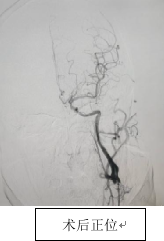

手术在局部麻醉下进行,王建峰主任亲自上台,操作精细,在BASIS技术辅助下,顺利通过闭塞段,成功恢复左侧颈内动脉血流。手术过程中未出现血栓脱落等并发症,术后患者生命体征平稳,已安全送回病房,在护理团队的共同努力下,朱先生恢复良好。

从治疗传统疾病的经验累积,到面对突发情况以及危重病例的精巧应变,充分反映出我院神经内科深厚的技术经验,以及我院多学科会诊的紧密协作能力,此次手术的顺利完成,标志着我院在复杂脑血管病治疗领域迈上新台阶。未来,我院将继续在新技术应用、精准诊疗和医护一体化服务方面不断提升,为患者提供更优质、安全的医疗保障。